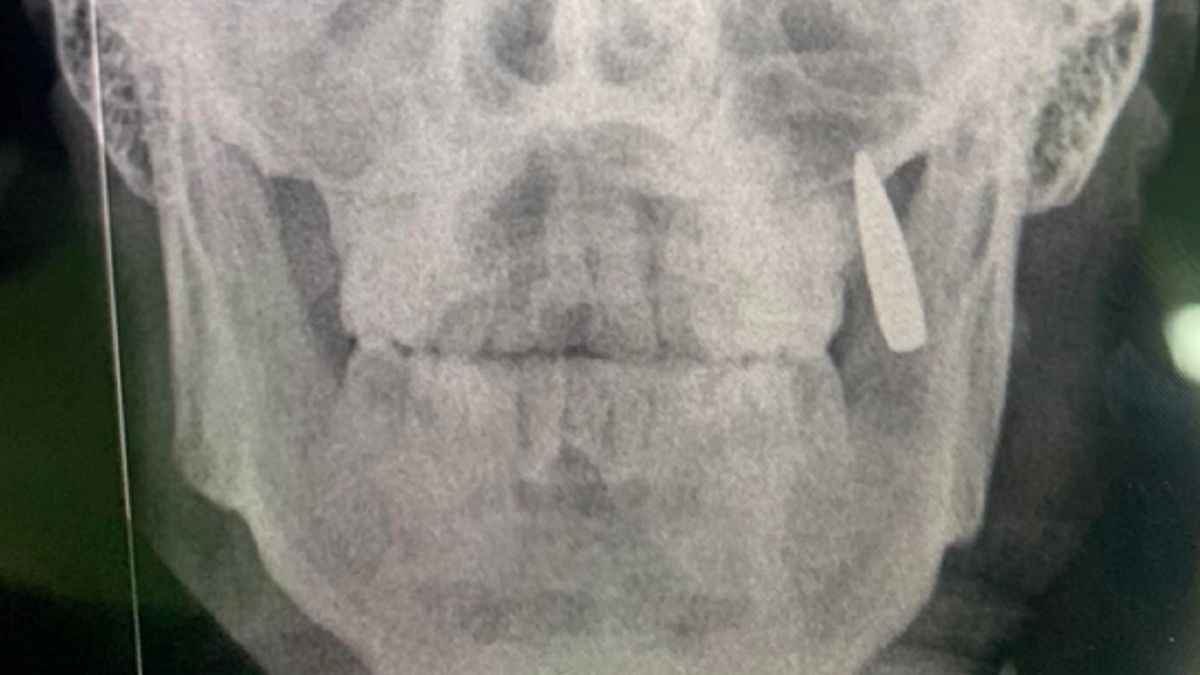

Nabój utkwił w szczęce żołnierza.Nabój utkwił w szczęce żołnierza.

Po zrobieniu zdjęcia rentgenowskiego okazało się, że w twarzy żołnierza znajduje się... pocisk. To właśnie nabój wybił dwa zęby mężczyzny i utkwił w ich miejscu. Na szczęście obrażenia spowodowane tym nabojem nie były groźne.

Robię rentgen, zamiast dwóch zębów kula utknęła w szczęce. No, to jest implant... - dodała Oksana.